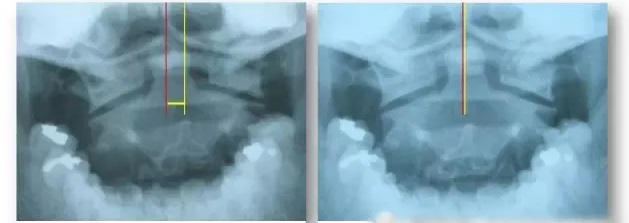

误区之八:颈椎生理弧度变直或反弓了就不能恢复正常了现代人因为生活和工作方式的变化,整天低着头的时间越来越多了,久而久之,颈椎正常的生理弧度(弧顶是向前的)渐渐减小、消失、甚至反弓(弧顶向后了)。这 种情况是引发颈椎病的重要原因之一,而且,如果生理弧度未能得到较好的恢复,颈椎周围的力学环境始终处于不良状态,颈椎病的病情就不容易稳定,因此,颈椎 生理弧度不是能不能恢复的问题,而是必须恢复的问题,它是治疗颈椎病的重要目标之一。

首先要知道牵引的目的是为了把椎体之间的距离拉大,减轻里面的压力,要达到这样的效果,牵引力的方向很重要,否则,力的作用部位偏了,该拉的地方没拉到,不需要拉的地方反而被拉伤了。如果是坐着牵引,正确的牵引力方向应该向前上方15º左右比较好。

另外要注意的是牵引疗法是一种权宜之计,疗程不宜过长,一般2周左右即可。因为生颈椎病的时候大多都会颈椎生理弧度变直,如果持续牵引则颈椎就无法恢复正常的生理弧度,颈椎及其周围的筋始终处于一个异常的力学环境内,颈椎病就很难痊愈。